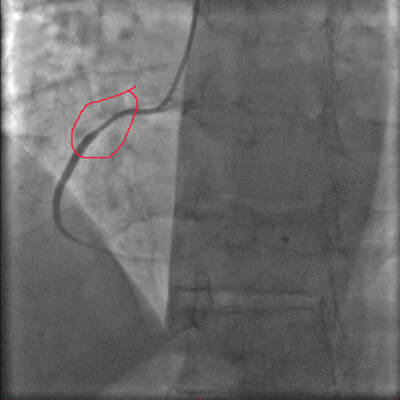

И что же там?? На коронарографии? Для краткости пару проекций (видео)

Пояснение - полная закупорка (стрелкой указано место где закрыт сосуд) передней межжелудочковой артерии - одна из самых важных в кровоснабжении сердца.